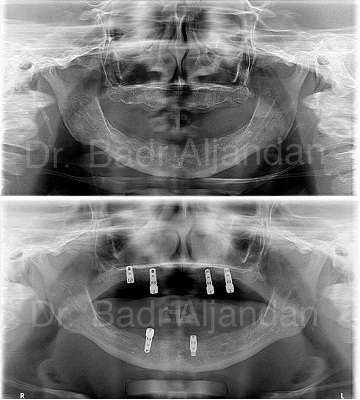

For most patients, the placement of dental implants involves two surgical procedures. First, implants are placed within your jawbone. For the first three to six months following surgery, the implants are beneath the surface of the gums gradually bonding with the jawbone. You should be able to wear temporary dentures and eat a soft diet during this time. At the same time, your dentist is forming new replacement teeth.

After the implant has bonded to the jawbone, the second phase begins. Dr. Al-jandan will uncover the implants and attach small posts that protrude through the gums and will act as anchors for the artificial teeth. When the artificial teeth are placed, these posts will not be seen. The entire procedure usually takes six to eight months. Most patients experience minimal disruption in their daily life.

Dental Implant placement is a team effort between an oral and maxillofacial surgeon and a restorative dentist. While Dr. Al-jandan performs the actual implant surgery, initial tooth extractions, and bone grafting if necessary, the restorative dentist (your dentist) fits and makes the permanent prosthesis. Your dentist will also make any temporary prosthesis needed during the implant process.

A single prosthesis (crown) is used to replace one missing tooth – each prosthetic tooth attaches to its own implant. A partial prosthesis (fixed bridge) can replace two or more teeth and may require only two or three implants. A complete dental prosthesis (fixed bridge) replaces all the teeth in your upper or lower jaw. The number of implants varies depending upon which type of complete prosthesis (removable or fixed) is recommended. A removable prosthesis (over denture) attaches to a bar or ball in socket attachments, whereas a fixed prosthesis is permanent and removable only by the dentist.

Dr Al-jandan performs in-office implant surgery in a hospital-style operating suite, thus optimizing the level of sterility. Inpatient hospital implant surgery is for patients who have special medical or anesthetic needs or for those who need extensive bone grafting from the jaw, hip or tibia.